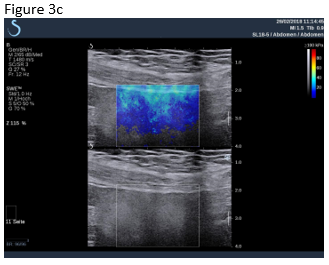

Figure 3: A follow up examination few weeks later revealed partially revascularised omental tissue in a now asymptomatic patient (a,b). Shear wave elastography is shown where there is now only relatively soft (inflammatory) tissue (c).